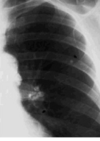

* Nombra el signo * ¿Qué tipo de estudio es? * Patrón observado

- **Líneas de Kerley** - RX - Reticular | (sólo se ven así en RX)